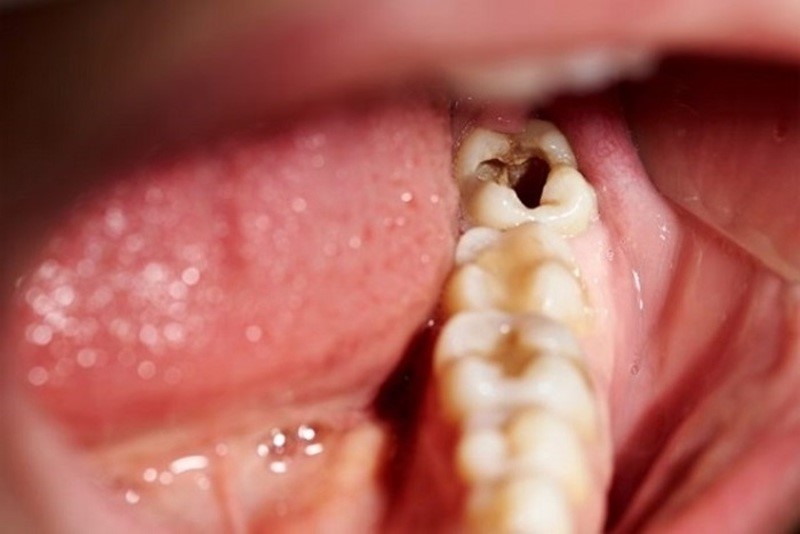

Vi khuẩn gây sâu răng không chỉ tấn công ở men răng mà chúng còn thâm nhập vào lớp ngà răng, tủy răng gây đau nhức dữ dội. Nếu không tiến hành khắc phục sớm bệnh có thể gây ra các biến chứng như viêm tủy răng, nhiễm trùng, răng gãy còn chân, răng lung lay thậm chí là mất răng sớm.

(Viêm tủy răng gây đau nhức dữ dội, ảnh hưởng nghiêm trọng đến lối sống của người bệnh)(**)

Sâu chân răng khi tiến triển nghiêm trọng sẽ gây ra các cơn đau, ê buốt răng dữ dội. Điều này sẽ làm suy giảm khả năng ăn nhai, người bệnh sẽ trở nên lười ăn uống hơn.